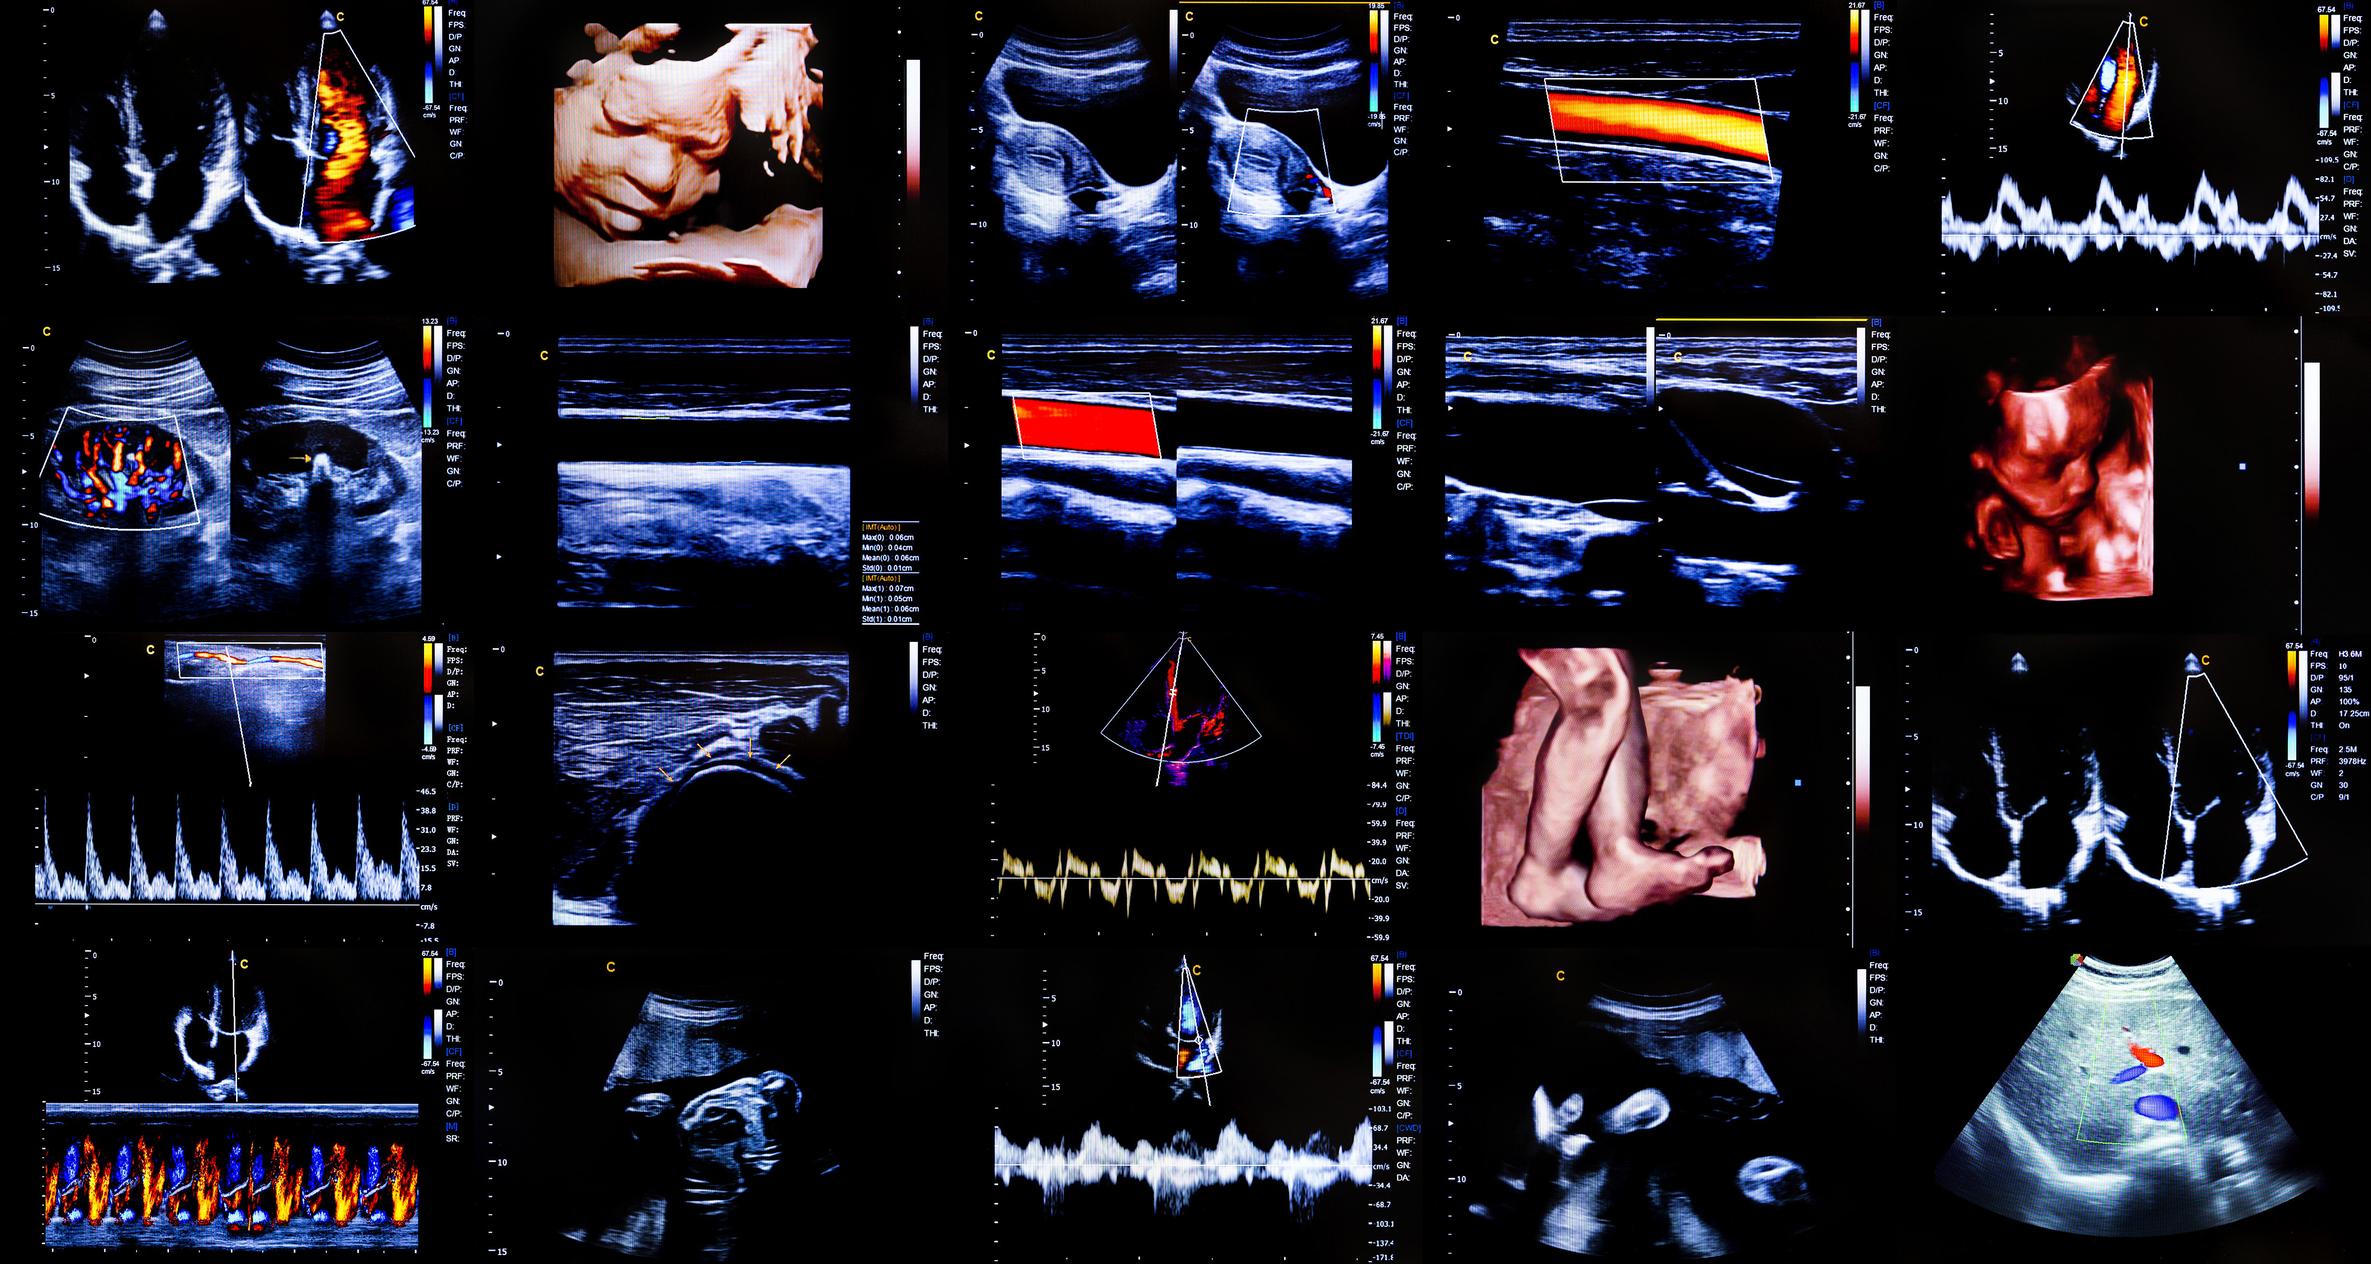

Ultrasound imaging is based on the principle of sound wave reflection. High-frequency sound waves (typically 2 to 20 MHz in medical contexts) are transmitted into a medium. When these waves encounter a boundary between different tissues or materials, they reflect back to the source. By measuring the time it takes for the echoes to return and their amplitude, it is possible to reconstruct an image of the internal structure.

The device that performs this task is called a transducer, which both emits and receives ultrasound waves. The echoes are processed by a computer and displayed as visual information, usually in shades of grey to indicate tissue density or structure.

Perhaps the most widely recognised use of ultrasound is in obstetrics. Expectant parents often encounter their first ultrasound during pregnancy. These scans provide essential information about foetal development, heartbeat, and anatomical abnormalities. More advanced 3D and 4D ultrasound techniques enable volumetric imaging and real-time motion capture, providing more detailed views of the foetus.

Ultrasound plays a central role in cardiac diagnostics through echocardiography. This technique allows clinicians to assess heart structure, function, and blood flow. Doppler ultrasound, a specialised form of the technique, measures the direction and speed of blood flow, aiding in the diagnosis of conditions such as valve disorders, congenital heart defects, and arterial blockages.

Abdominal ultrasound can detect issues in various organs, including the liver, kidneys, pancreas, and gallbladder. Similarly, musculoskeletal ultrasound helps visualise muscles, tendons, and joints. It is particularly useful for guiding injections and assessing soft tissue injuries.

Ultrasound is frequently used to guide interventions such as biopsies, drainage procedures, and regional anaesthesia. By allowing for real-time visual confirmation of needle placement, ultrasound enhances accuracy and safety.

Three-dimensional ultrasound reconstructs volumetric images, giving a more complete representation of anatomical structures. When updated in real-time (4D), these images facilitate dynamic assessments—for instance, observing heart valves in motion or foetal movement during pregnancy.